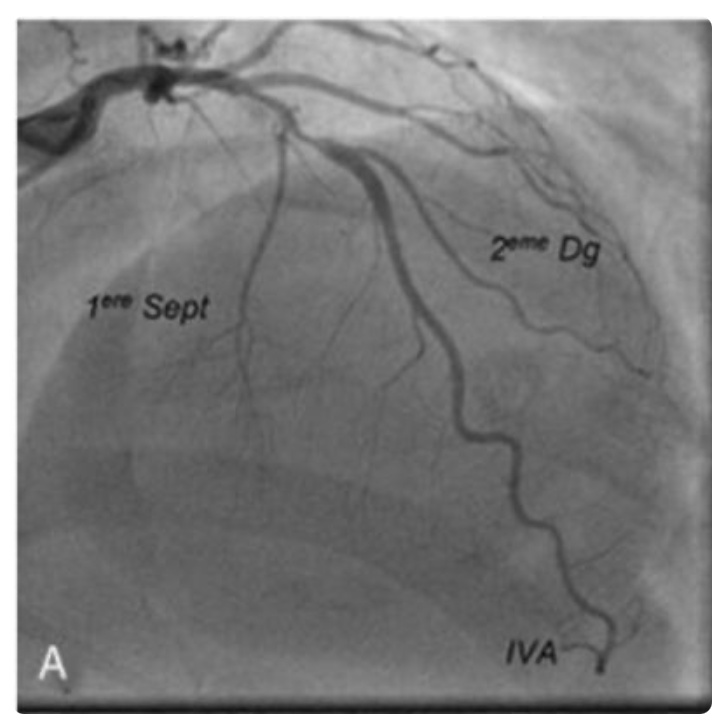

Concernant cet examen : (cf photo)

C’est bien une coronarographie.

Le B correspond à une diagonale !